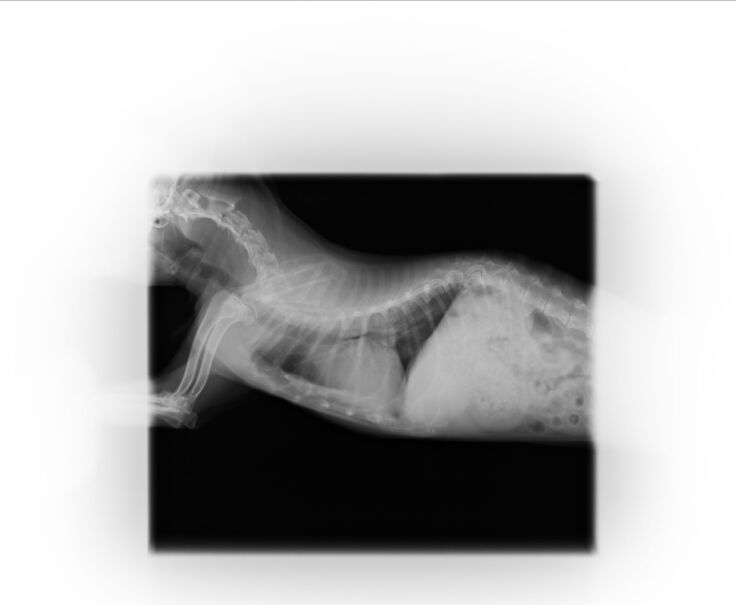

ーーーーー以下参考資料ーーーー

現在通院している病院の物です。

以下レントゲン写真